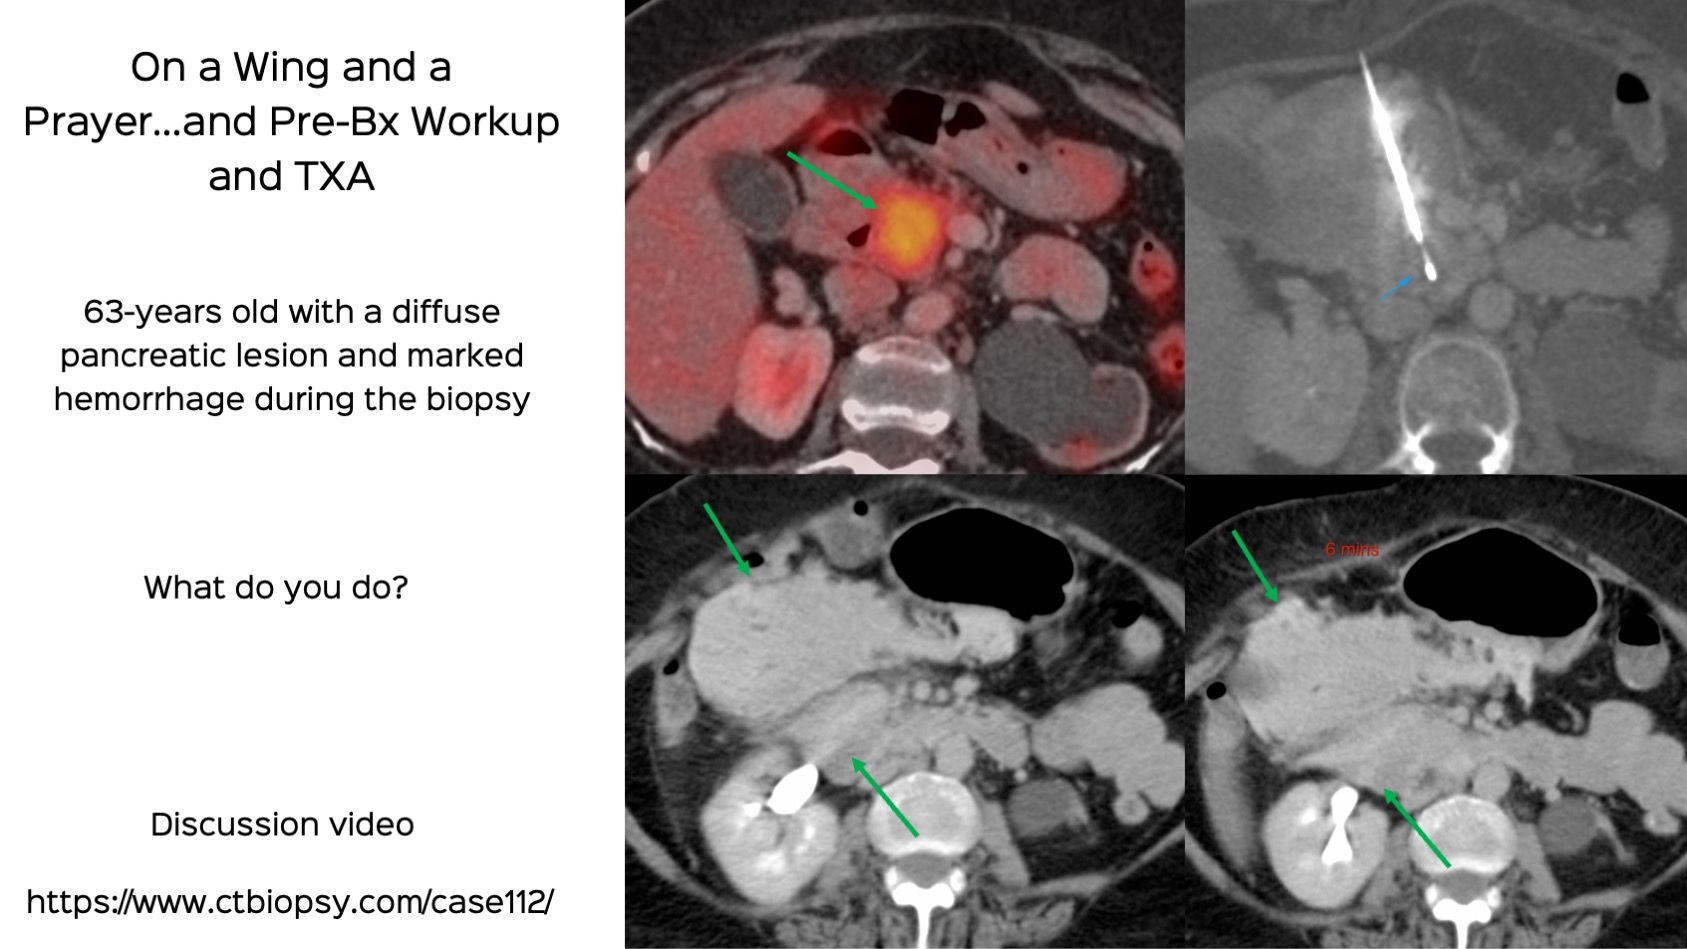

Case 112: Pancreatic Head Biopsy and Hemorrhage - On a Wing and a Prayer...And Pre-Bx Workup and TXA